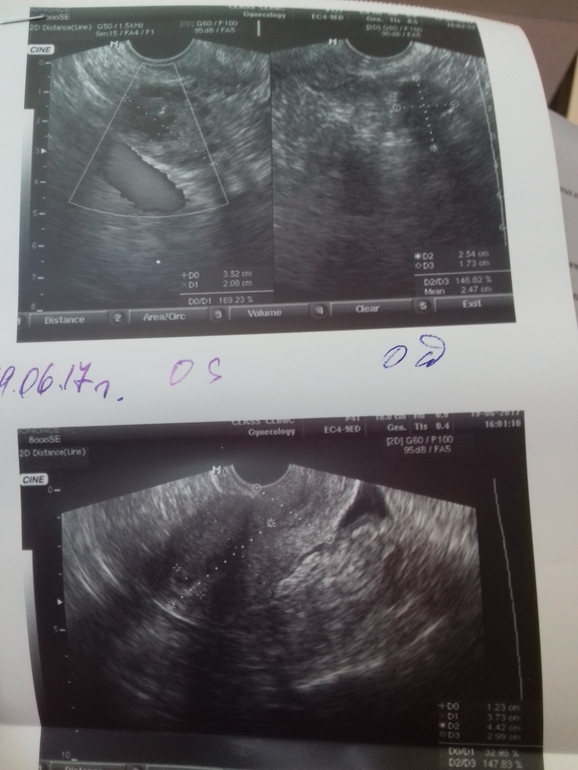

Овуляция( тесты на овуляцию)Всем приветики. Сходила на узи,только приехала. Овуляция прошла. Получается сегодня 2дпо. Жт 20×23мм с умеренным кровотоком,хорошее жт,стенки его утолщаются узистка сказала. Эндик 12мм трехслойный.